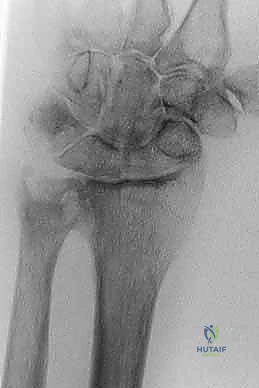

Figure 1: Radiographs from a patient with rheumatoid arthritis before (A) and after (B,C) a Sauvé-Kapandji procedure. The ulnar osteotomy allows for precise shortening to establish neutral ulnar variance while preserving functional forearm rotation.